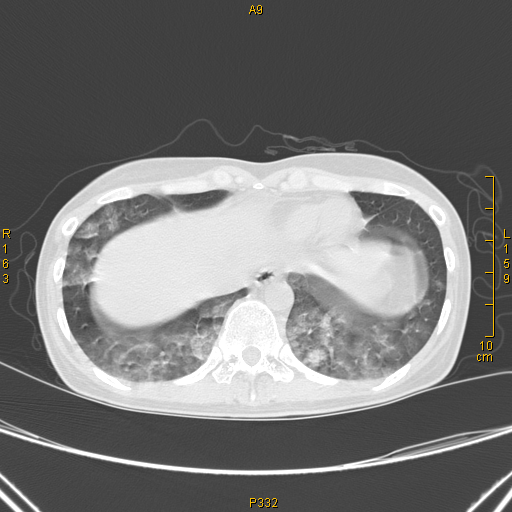

病例68——肺部典型病例(吸入性肺炎) - 医学影像学讨论版 - 爱爱医

吸入性肺炎一例(游泳呛水引起)ct图片.

同时复查,病人肺部ct.病人发病时,吸入咖啡色胃内容物导致吸入性肺炎